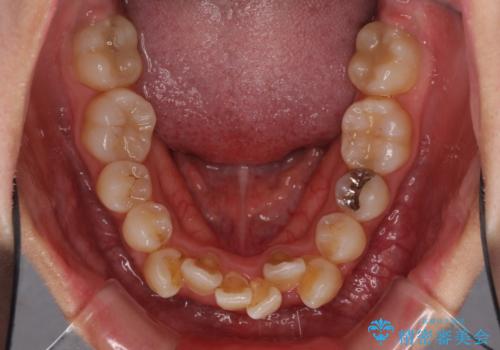

- 上下前歯のデコボコと、それによる磨きづらさを気にして来院された患者様です。

叢生解消のため、上下左右第一小臼歯4本を抜歯し、ワイヤー装置にて矯正治療を行うこととしました。